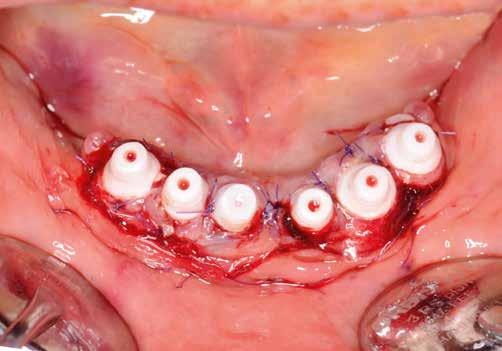

2. kép: 6 egyrészes SDS kerámiaimplantátum azonnal behelyezve az extrakciót követően.

Terápia és implantáció

Az operatív beavatkozás előtt a behelyezett fogsorokkal és azok nélkül is beszkennelték az intraorális szituációt, valamint elkészítették a fogsorok digitális másolatát. Ezután óvatosan kihúzták a maradék fogakat, és mindent előkészítettek az azonnali implantációhoz, amelynek során 6 egyrészes SDS kerámiaimplantátumot terveztek behelyezni a meglévő alveolusba a 34-43 közötti területre. Közvetlenül a behelyezést megelőzően a szék mellett még egyszer megtisztították Diener Denta Plas plazmakészülékkel (lásd 49. kép) az implantátumokat, a lehető legteljesebb csírátlanítás – így a páciens csíraterhelésének minimalizálása – érdekében (2. kép) Az alveolus ózonos tisztítását követően behelyezték a hat egyrészes SDS kerámia-implantátumot, A-PRF (saját vérlemezkében gazdag – a ford.) membránokkal megsegítve. A laborkészítésű előre mintázott elemek alapján azonnali ide-

iglenes került az implantátumokra (3. kép), majd röntgennel újólag ellenőrizték a létrejött helyzetet (4. kép)